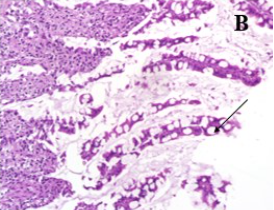

Kết luận: Các bệnh tích đại thể ở dạ dày, ruột gồm sung huyết, niêm mạc xuất huyết, chất chứa trong lòng ruột có mùi tanh máu. Bệnh tích vi thể rõ nhất ở ruột với nang lympho thành ruột tăng sinh, thoái hoá tế bào biểu mô, lông nhung đứt gãy. Bệnh tích của hạch lympho cho thấy số lượng bạch cầu lympho giảm mạnh ở vùng vỏ các nang hạch màng treo ruột; bạch cầu đơn nhân lớn và đại thực bào tăng mạnh. Các bệnh tích khác quan sát được gồm viêm kẽ phổi, viêm phế quản phổi và tăng sinh các vùng tuỷ trắng trong mô lách.

| Hình A. Nang lympho thành ruột tăng xinh (X100) | Hình B. Tế bào biểu mô ruột thoái hoá (X400) |